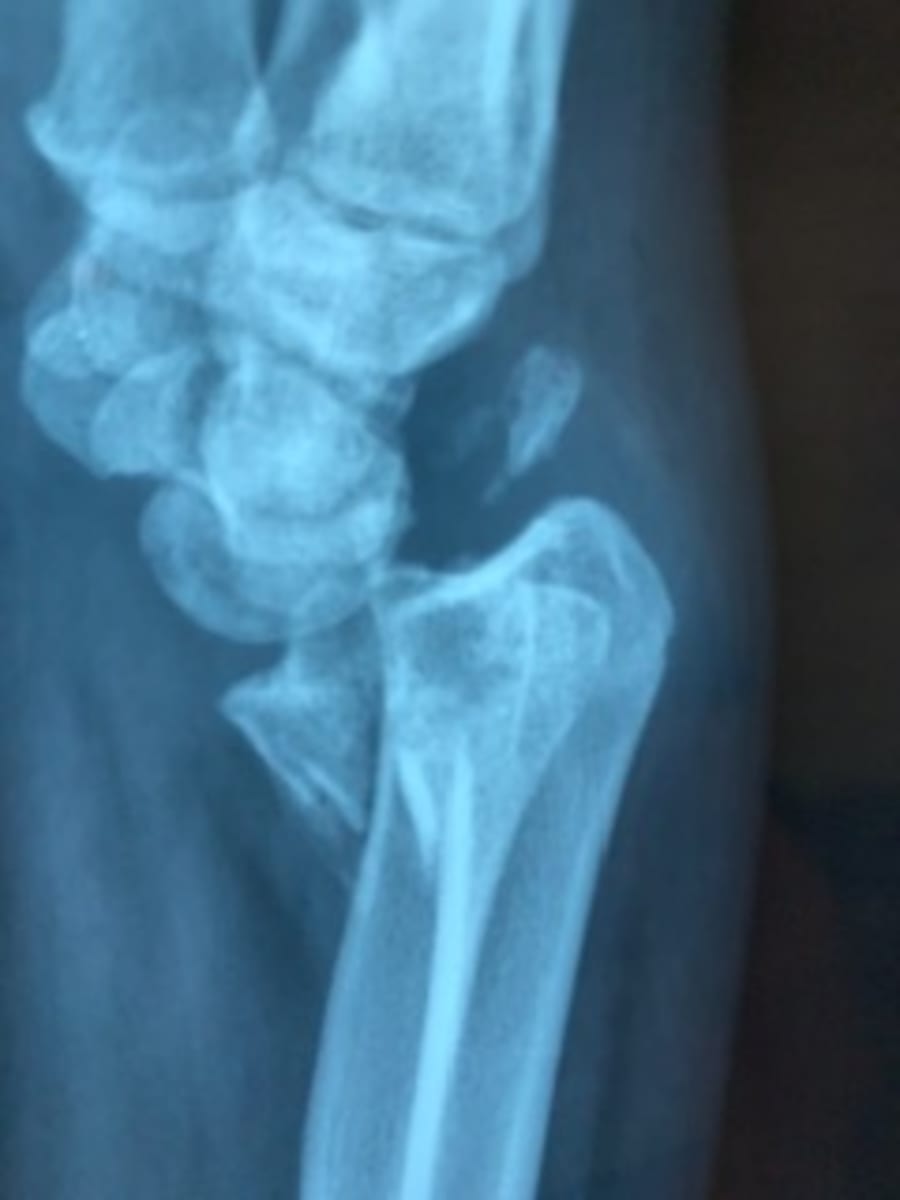

A few examples of the patients and conditions we treated are now presented. Images 2-4 are of an 8 year old boy with symbrachydactyly. He required syndactyly release of the first web space and z-plasty of the small finger. Images 5-6 are of a patient with a severe wrist flexion contracture due to longstanding neuromuscular disorder. Image 6 is an intraoperative photo of his fused wrist. Images 7-8 are of a patient with a benign bone tumor. Images 9-11 demonstrate treatment of a patient with a distal radius fracture. In the US, this would be fairly easily treated with early open reduction and internal fixation. This fracture was made more challenging in that it was eight months old. On rare occasions, we are also able to treat acute fractures.